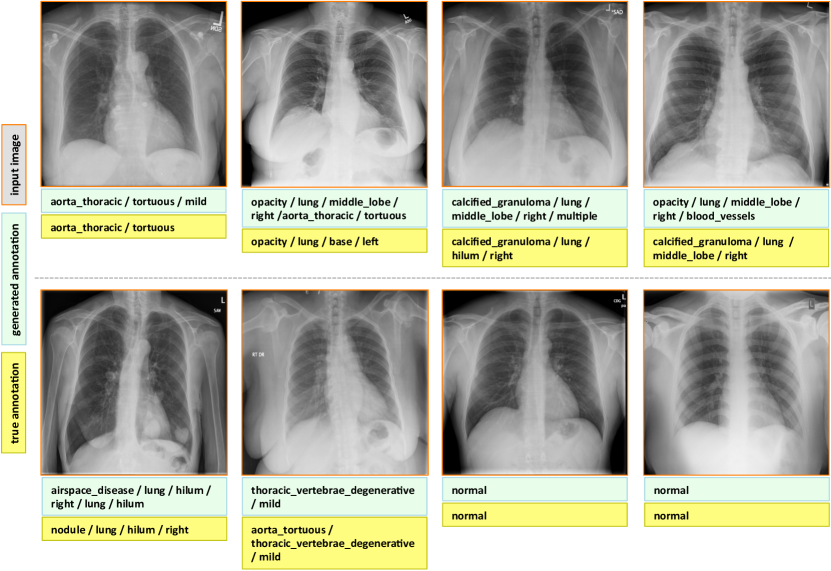

7.1 Evaluation

The final evaluated BLEU scores are provided in Table 5. We achieve better overall BLEU scores than those in Table 4 before using the joint image/text context. It is noticeable that higher BLEU-N () scores are achieved compared to Table 4, indicating that more comprehensive image contexts are taken into account for the CNN/RNN training. Also, slightly better BLEU scores are obtained using GRU on average and higher BLEU-1 scores are acquired using LSTM, although the comparison is empirical. Examples of generated annotations on the chest x-ray images are shown in Figure 6. These are generated using the GRU model, and more examples can be found in the supplementary material.

Appendix C More Annotation Generation Examples

More annotation generation examples are provided in Figures 10 and 11. Overall, the system generates promising results on predicting disease (labels) and its context (attributes) in the images. However, rare disease cases are more difficult to detect. For example, the cases pulmonary_atelectasis, spondylosis, and density (Figure 10), as well as foreign_bodies, atherosclerosis, costophrenic_angle, deformity (Figure 11) are much rarer in the data than calcified_granuloma, cardiomegaly, and all the frequent cases listed in Table 1 of the main paper.

Furthermore, the (left or right) location of the disease cannot be identified in a lateral view (obtained by scanning the patient from the side), as shown in Figure 11. Since our dataset contains a limited number of disease cases, we treat each x-ray image and report as a sample, and do not account for different views.

For future work, we plan to improve prediction accuracy by both (a) accounting for the different views, and (b) collecting a larger dataset to better account for rare diseases.